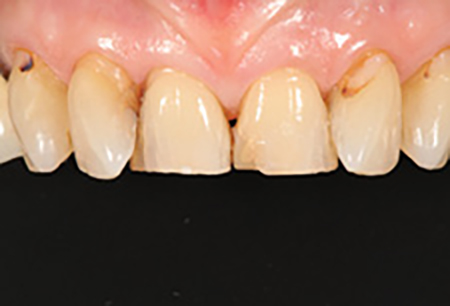

A 67-year-old female executive presented after becoming very self-conscious about the appearance of her anterior teeth (figure 1). During the consultation appointment, a thorough examination was performed, and scanned intraoral 3-D images and impressions (Trios, 3Shape) were obtained. Both arches and the bite registration were scanned (figure 2).

Figure 1: Preoperative retracted view of a female patient’s maxillary anterior teeth showing lingually positioned central incisors due to severe crowding of her arch